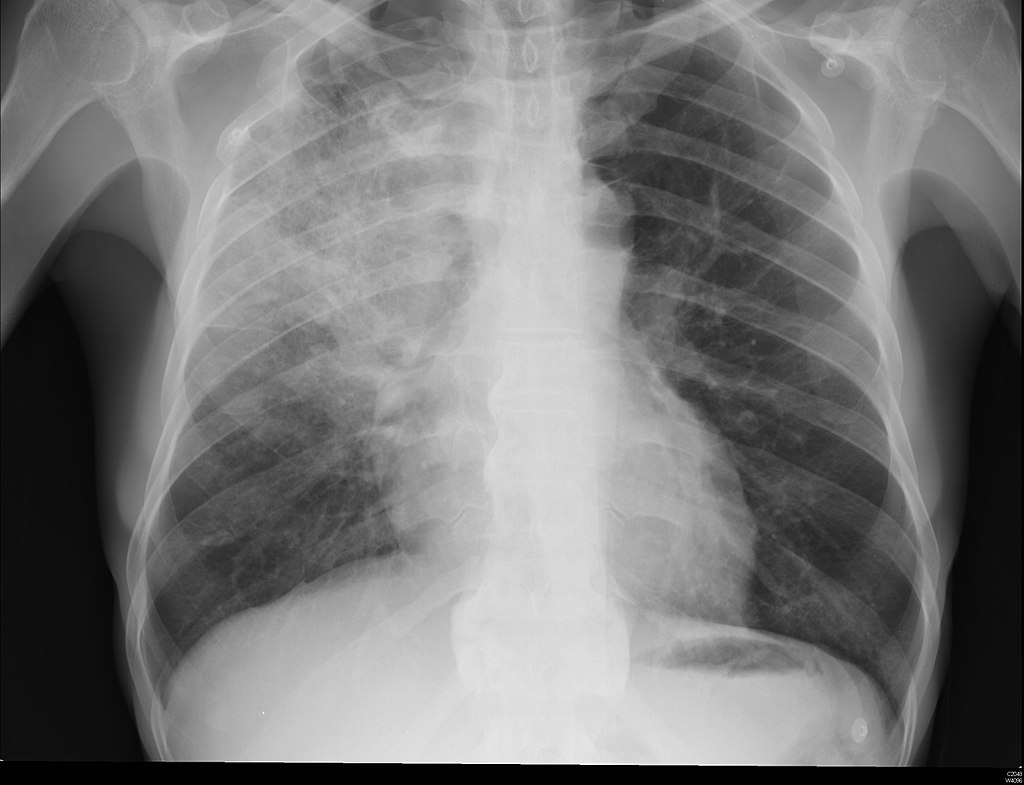

All patients age 18 or older with a chest x-ray demonstrating pneumonia were eligible for the algorithm, which was available but not mandatory for ED physicians. Over 18 months, data were collected on 4,500 or so patients with a median age of 67, 48 female, and 94% White. Outcomes included appropriate antibiotic selection, placement (out or inpatient), and mortality; a cohort of patients treated before implementing the algorithm served as controls.